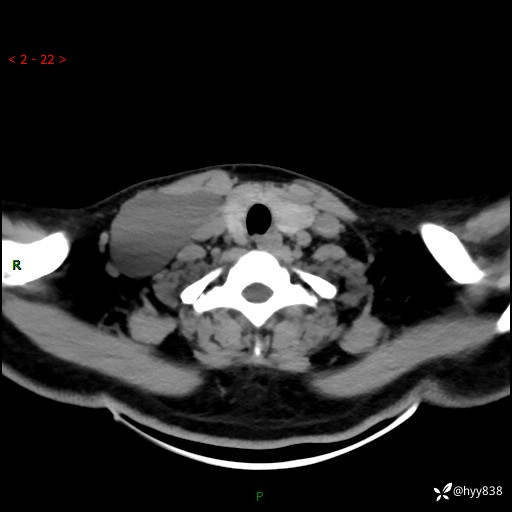

辅助检查:CT

颈部CT平扫

增强动脉期+静脉期